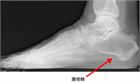

1. 足底腱膜炎は、炎症ではなく過負荷が原因で起こる足底腱膜の微小断裂である。